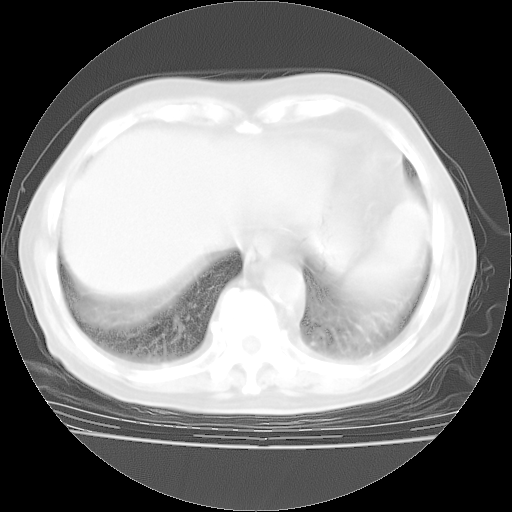

4月28日肺部CT——再次出现类似去年5月9日——透光度降低,“间质性”改变。